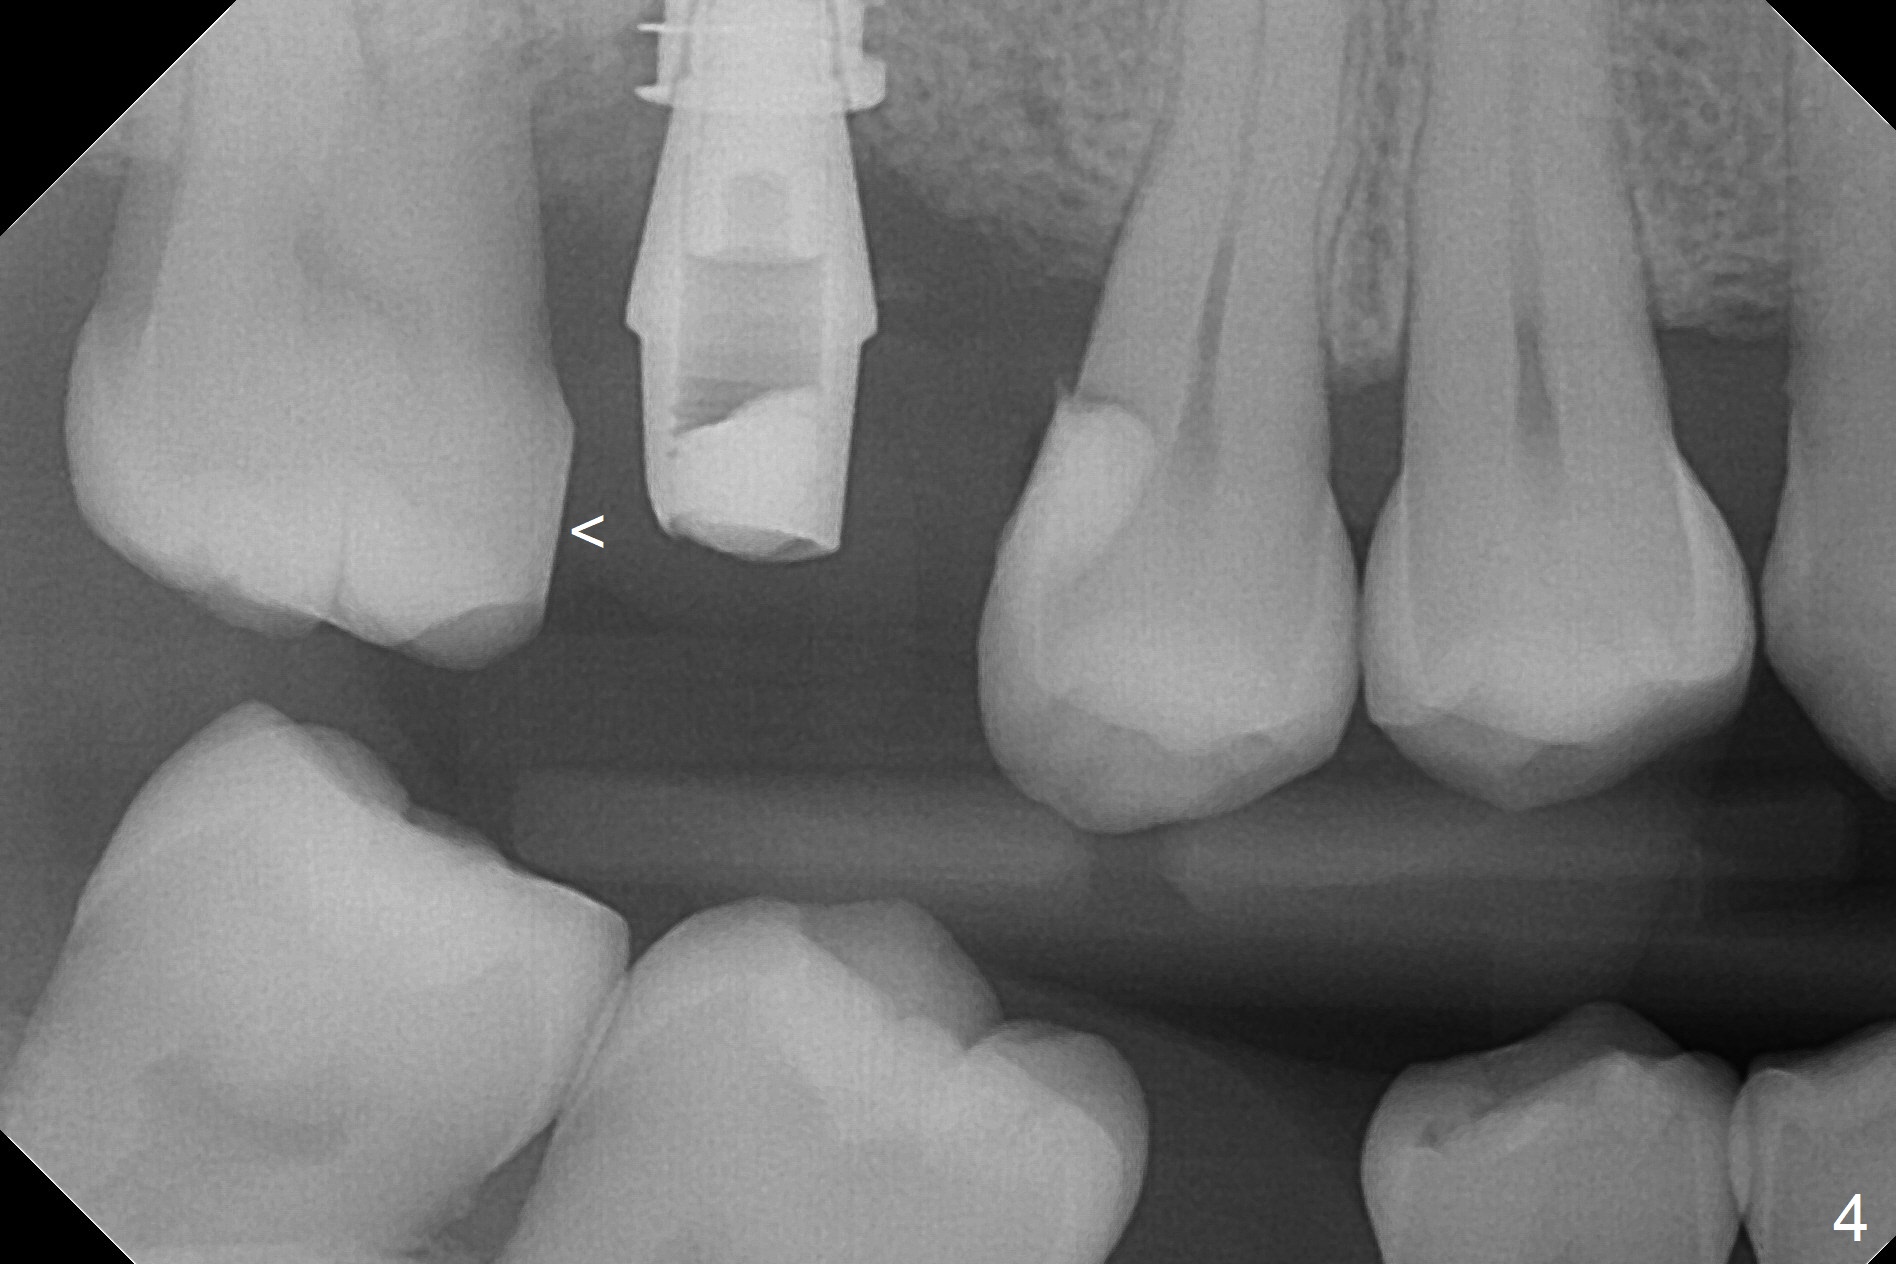

There are 2 sockets at #3 when the residual roots are extracted; osteotomy is established in the palatal one for 11 mm (gingival level; Fig.1), ~ 2 mm from the sinus floor (red dashed line). Following the last drill (3.8 mm) for 11 mm, a 4.5x11 mm dummy implant is placed 2 mm subgingival (Fig.2). In fact the sinus lift (red dashed line) is done by implant insertion, since the bone plug after Magic Drill is present in the apical portion of the osteotomy when the last drill is finished prior to implant placement.. After the dummy implant is removed, the definitive one (the same size) is placed with >50 Ncm, followed by placement of a 4.5x4(3) mm abutment and VeraGraft mixed with autogenous one (Fig.3 *). The most coronal portion of the socket is sealed with collagen plug. The latter is fixed in place by an immediate provisional. The mesial surface of the tooth #2 is reduced (Fig.4 <) prior to provisional fabrication. The implant is placed distal, which could be corrected by pushing the 2nd molar distal orthodontically. There is mild crestal bone loss nearly 8 months postop (Fig.5). An angled abutment (5x15 degrees, 3 mm cuff) is used before impression. CT is taken immediately post cementation (Fig.6 (8.5 months postop)). CT taken 8 months post cementation shows that the 4.5x11 mm implant barely passes the sinus floor (Fig.7). Return to Upper Molar Immediate Implant, Prevent Molar Periimplantitis (Protocols, Table), IBS, 30 19 Xin Wei, DDS, PhD, MS 1st edition 09/13/2017, last revision 01/31/2019